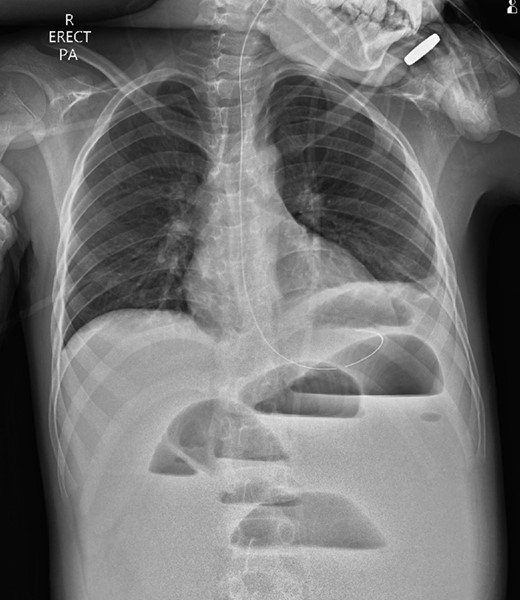

A 10-year-old boy presented unwell with generalized peritonitis after 3 days of abdominal pain, nausea and anorexia. He had a low-grade fever but all other vitals were within normal limits. Blood tests showed a raised white cell count of 16 × 109 with neutrophilia and raised C-Reactive Protein of 127 mg/l. Laparoscopy revealed generalized purulent peritonitis secondary to perforated appendicitis. Appendicectomy was performed and the appendiceal stump was secured. Lavage of the abdomen was performed with a minimum of four litres of warmed normal saline. Fluid was suctioned, an abdominal drain was placed and the pneumoperitoneum was deflated. By the second postoperative day, he developed an ileus with persistent vomiting (Fig. 1). This was managed conservatively with nasogastric intubation, bowel rest, electrolyte replacement and fluid therapy. It became clear by the fifth postoperative day that the patient had intestinal obstruction. On examination, he had a distended abdomen, with intractable nausea and vomiting. Blood tests revealed a normal white cell count and potassium remained at 3.3 despite supplemental intravenous replacement. Abdominal X-ray revealed a small bowel obstruction and he was taken back to theatre for an emergency laparotomy (Figs 2 and 3). A small bowel volvulus was discovered, with no evidence of intestinal malrotation. The volvulus involved a segment of distal jejunum to proximal ileum causing complete small bowel obstruction.

Supine abdominal radiograph on day 5 showing dilated small bowel loops with no bowel gas evident in the colon.